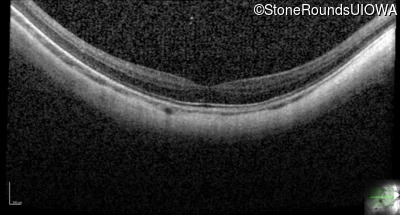

AR CSNB, normal fundus (IA2fiii)

Age at visit: 16 years

This 16 year old male has had poorer vision in dim light than his siblings since childhood. He has also been very myopic since childhood and is currently wearing -14.00 diopter spectacles. The maximum combined response of the electroretinogram reveals a selective loss of the b-wave.

AR CSNB, normal fundus TRPM1 Lys18 del18aAGGTGAGTGAGCTTTGCC Tyr72Cys TAT>TGT AR